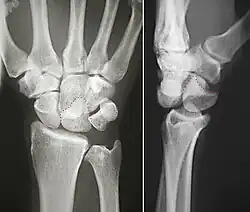

The lunate bone is the most frequently dislocated carpal bone.

Dislocated lunate -